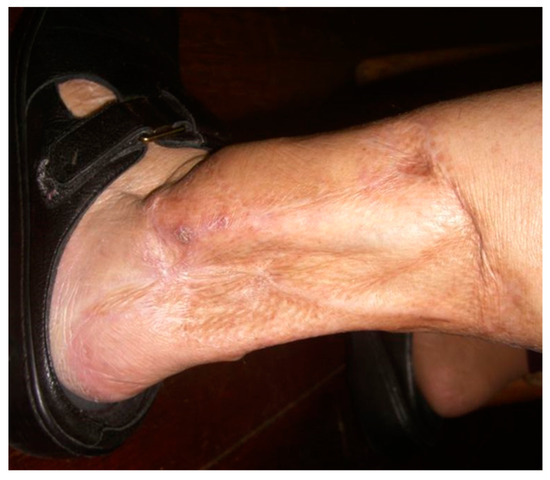

Chronic venous insufficiency is a cause of venous leg ulcers, the most common type of leg ulcers. These are frequently located in the gaiter region, an area between the midcalf and the ankle. Venous ulcers tend to recur and require frequent healthcare provider visits to dress the wound. This poses a significant cost burden to the patient while decreasing the quality of life [49]. Normally, retrograde venous blood flow is prevented by one-way valves that open toward the deep veins. In patients with venous insufficiency, this process is impaired, causing inappropriate transmission of blood from deep veins to superficial veins [50]. This results in varicose veins where the normal vein wall architecture is disrupted and “venous hypertension” which can lead to ulceration (Figure 5).

The pathophysiology of venous ulceration is complex but has become more fully understood over the last two decades. Current theories suggest that venous hypertension elicits a state of chronic inflammation in which the constant recruitment of white blood cells leads to tissue injury [51]. Increased pressures in the vessels lead to extravasation of inflammatory agents, such as fibrinogen and iron from red blood cell degradation [52]. The inflammatory signals result in the recruitment of macrophages and mast cells, which release transforming growth factor beta-1 (TGF-β1) and histamine, respectively. TGF-β1 inhibits fibroblast proliferation, impairing collagen production. Lastly, due to iron overload, macrophages fail to polarize to the M2 phenotype required for extracellular matrix deposition and therefore, proper wound healing [51]. At the molecular level, the regulation of tissue oxygen content is obviously critical. Hypoxia-inducible factors (HIFs) are integral to this important regulatory network, functioning as oxygen sensors. Prolyl hydroxylase, responsible for adding –OH to carbon 4 of the imino ring of proline residues in type I collagen using molecular oxygen, is a member of the 2-oxoglutarate, also known as α-ketoglutarate, -dependent dioxygenases family. The prolyl hydroxylase domain (PHD)-containing proteins also hydroxylate proline residues in HIF-1α and HIF-2α in the presence of Fe2+. Chronic open wounds with exposure to atmospheric O2 cause excessive Fe3+ production and interfere with prolyl hydroxylase and HIF function [53]. Importantly, iron through a Fenton reaction in an oxidative environment, generates an extremely reactive hydroxyl radical, OH., which can cause extensive oxidative damage to the organelles [54].